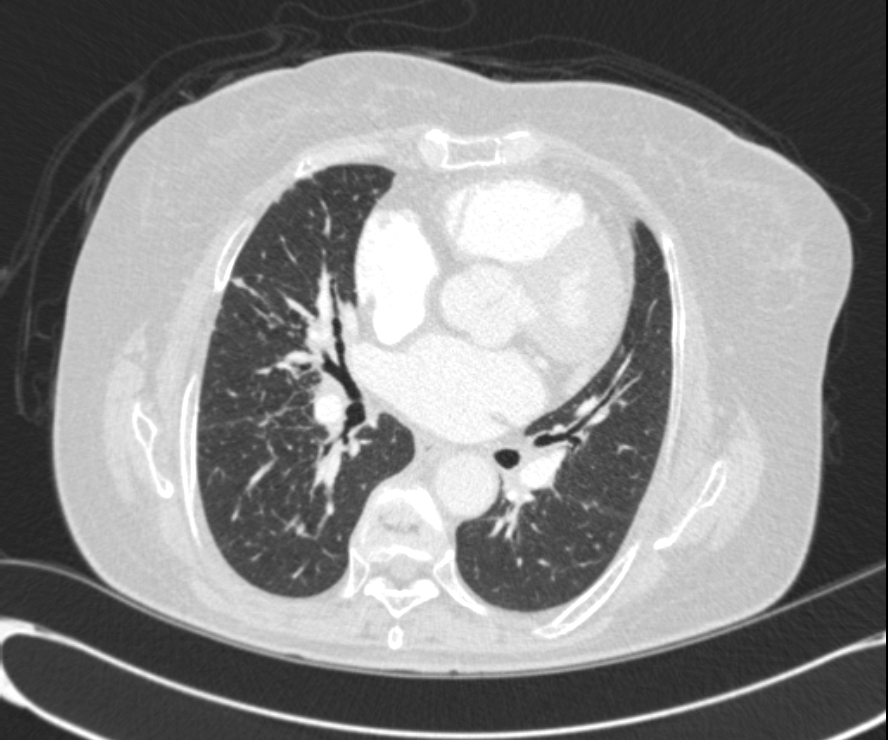

* CXR °ú  chest CT  »çÁøÀÔ´Ï´Ù.

¶Ñ·ÇÇÑ ¿µ»óÀ» À§ÇØ f/u Áß¿¡ ÂïÀº »çÁøÀ» ÷ºÎÇÏ¿´½À´Ï´Ù.

l  Chest CT

Progression of multiple small nodules in both lungs, along peri-BV and ILS, dominant on RUL and RML. No significant change of several small LNs in both hilar and mediastinum.   COPD: diffuse bronchitis. LH enlarge and PAH.